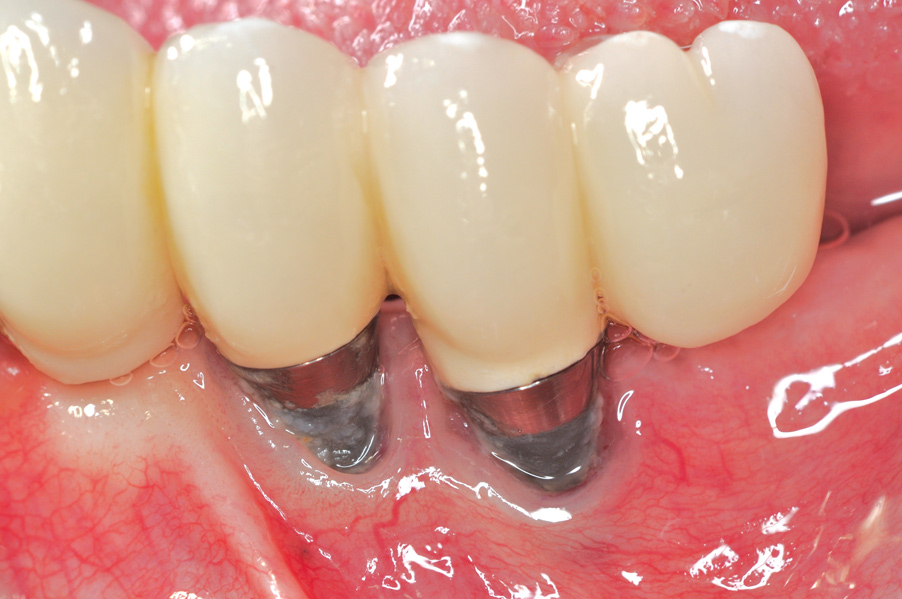

Dental implants have revolutionized the way in which clinicians treat and restore partially and fully edentulous patients and have demonstrated success for managing a broad range of clinical dilemmas. While implants have been highly predictable and have achieved long-term success, they are not immune from complications associated with improper treatment planning, poor surgical and prosthetic execution, material failure, and inadequate or infrequent maintenance. Among these problems are the biologic complications of peri-implant mucositis and peri-implantitis, which are inflammatory conditions in the soft and/or hard tissues surrounding dental implants (Figure 1 through Figure 4).1,2